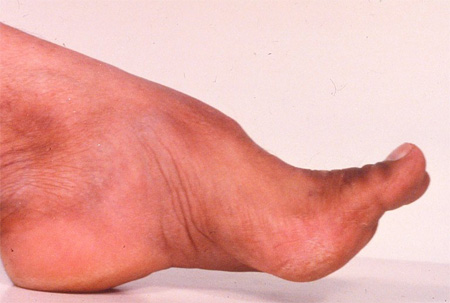

Many of these cases, including most children with Friedreich's ataxia, have absent tendon reflexes, reflecting co-existent peripheral nerve disease. Rarer diseases can have associated spasticity and brisk tendon reflexes. Eye movement apraxia is seen (but not universally) in AT, AOA1, and AOA2. Associated choreic movements are also seen in AT, AOA1, and AOA2, but not in Friedreich's ataxia. Head tremor and retinopathy can be seen in ataxia with vitamin E deficiency (AVED) and retinopathy in mitochondrial DNA abnormalities. Pes cavus may be seen in Friedreich's ataxia. The patient should be examined for systemic abnormalities.[Figure caption and citation for the preceding image starts]: Pes cavus deformity in Friedreich's ataxiaFrom the collection of Dr S. H. Subramony; used with permission [Citation ends].